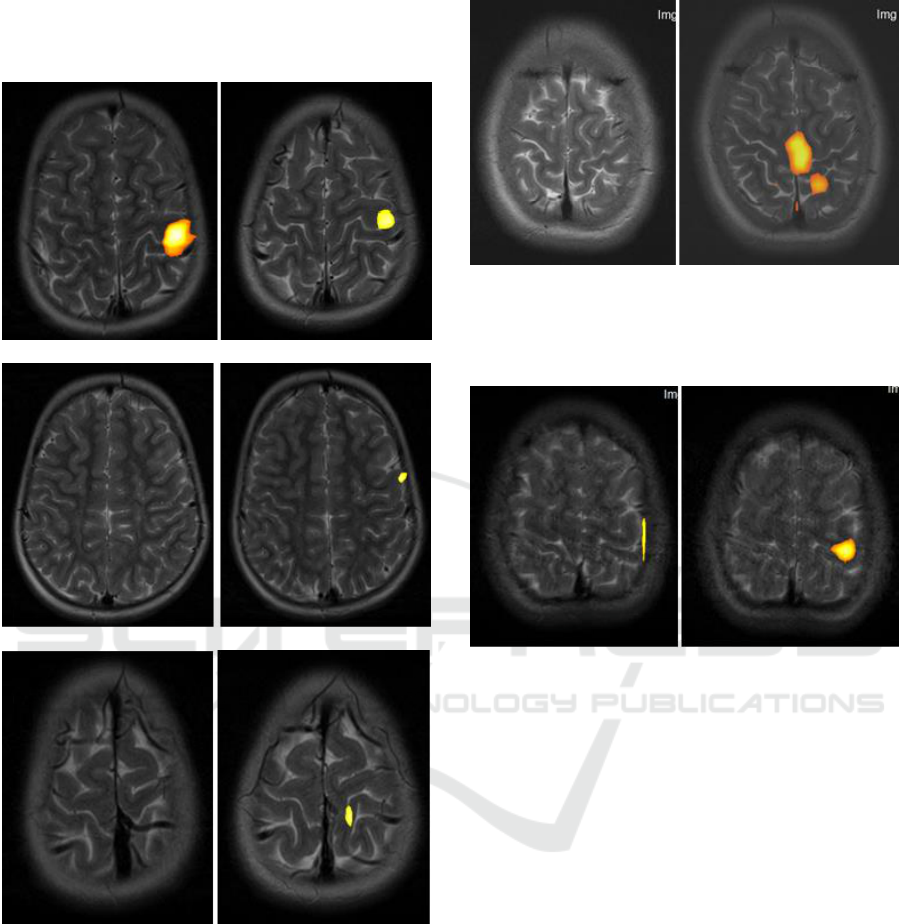

Wildenberg J., Tyler M.E., Danilov Y.P., Kaczmarek K.,

Meyerand M., 2013. Altered Cоnnectivity of the

Balance Proccessing Network After Tongue

Stimulation in Balance-Impaired Individuals. Brain

Connectivity, (10), 87-97.

Meyerand M., 2011. High-resolution fMRI defects

neuromodulation of individual brainstem nuclei by

electrical tongue stimulation in balance-impaired

individuals. Neuroimage, 56 (8), 2129-2137.

Meyerand M., 2011. Electical Tongue Stimulation

Normalires Activity Within the Motion-Sensitive Brain

Networt in Balance-Impaired Subjects as Revealed by

Group Indtpendent Component Analysis. Brain

connectivity, (3), 255-265.

Joseph C. Wildenberg, Mitchell E.Tyler, Yuri P. Danilov,

Kurt A. Kaczmarek, Mary E., 2011. Meyerand High-

resolution fMRI detects neuromodulation of individual

brainstem nuclei by electrical tongue stimulation in

balance-impaired individuals. Journal Neurolmage, (8),

2129-2137.